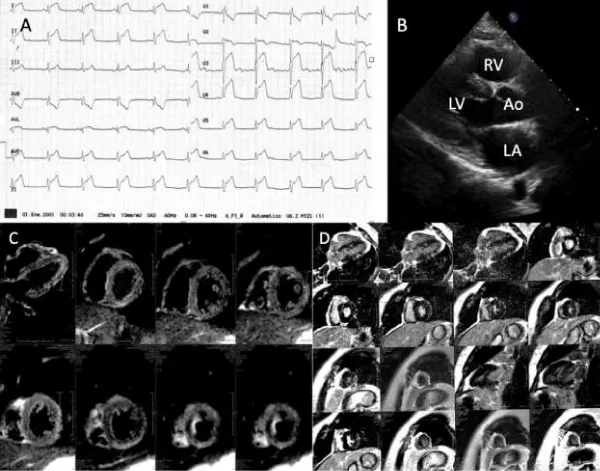

A 16-year-old man with history of two weeks-flu like symptoms with intermittent fever. He came to the emergency department with 2 hours-chest pain that radiates to the back and upper extremities. At the admission he was hemodynamically stable with normal blood pressure The ECG showed sinus rhythm and ST segment elevation of 0.5 mV in all leads (Figure 1A). The cardiac enzymes were elevated (Troponin 12.19 ng/mLland creatine kinase-MB fraction 63.25 U/L). He was admitted to the Intensive Care Unit and later transferred to our medical unit to continue with study protocol. The transthoracic echocardiogram (Figure 1B) reported normal left ventricular systolic function with left ventricular ejection fraction (LVEF) 68%, global longitudinal strain -18%, TAPSE 30 mm, and normal systolic pulmonary artery pressure (30 mmHg).

Figure 1:Acute viral myocarditis. A: Emergency department ECG that showed sinus rhythm and ST segment elevation of 0.5 mV in all leads. B: Transthoracic echocardiogram with normal diameters and systolic wall thickness. C,D: Cardiac magnetic resonance with late gadolinium enhancement in the left ventricular infero-lateral and inferior walls, suggestive of myocarditis.

The cardiac magnetic resonance imaging showed myocarditis with late gadolinium enhancement in the infero-lateral and inferior walls, without pericardial involvement, left ventricular global hipokinesia with LVEF of 53% and no valvular lesions (Figure 1C,D). Medical treatment was started with clinical improvement after 10 days. Also, the cardiac enzymes normalized (Troponin 0.37 ng/mL and creatine kinase-MB fraction 12.5 U/L.) During the 7 months follow-up he is in NYHA functional class I.